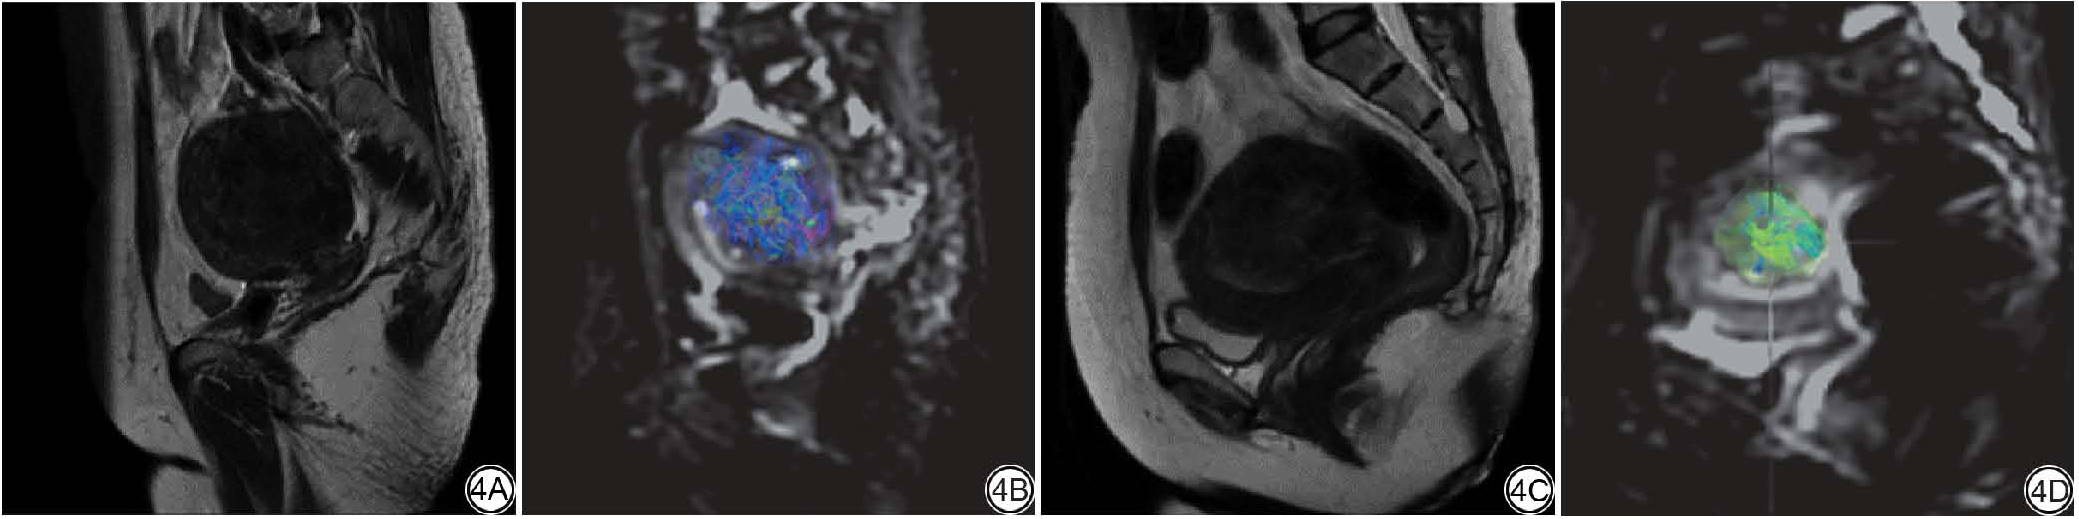

图1  女,37岁,子宫腺肌病病灶体积与非灌注体积比(NPVR)的感兴趣区(ROI)勾画示意图。1A:T2WI图,病灶呈等低混杂信号。1B:高强度聚焦超声(HIFU)术前增强MRI静脉期图像,病灶呈轻度强化。在体积加速肝脏采集序列(LAVA)序列图像上,对病灶区域逐层勾画。1C:HIFU手术后增强MRI静脉期图像,在LAVA序列图像上,对未显示对比剂强化的低信号区逐层勾画。1D:在术前图像上逐层勾画病灶感兴趣体积(VOI),获取消融后无灌注区域的体积。1E:在术后LAVA图像上勾画病灶VOI并计算消融后无灌注区域。

Fig. 1  Female, 37 years old, schematic illustration of region of interest (ROI) delineation for adenomyosis lesion volume and nonperfused volume rate (NPVR). 1A: On the T2WI, the lesion shows iso- to hypointense mixed signal. 1B: On the pre high intensity focused ultrasound contrast-enhanced MRI venous phase image, the lesion demonstrated mild enhancement and is delineated slice by slice on liver acquisition with volume acceleration (LAVA) images. 1C: On the post- high intensity focused ultrasound contrast-enhanced MRI venous phase image, the non-enhancing hypointense region is delineated slice by slice on LAVA images. 1D: The volume of interest of the lesion is delineated on pre-high intensity focused ultrasound contrast-enhanced MRI images to calculate lesion volume and derive the non-perfused volume. 1E: On post- high intensity focused ultrasound contrast-enhanced MRI images to calculate the nonperfused volume.